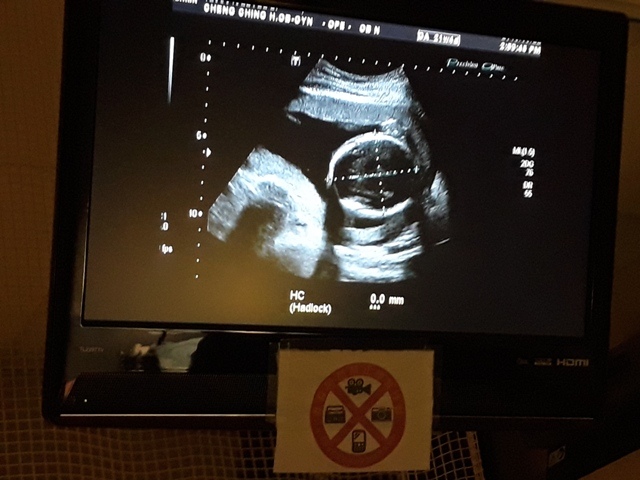

妊娠糖尿病數值為124,超過140就是超標,小純的妊娠糖尿病檢驗結果為正常的數值。接著,去照超音波,自從05月22日和06月03日的產檢,發現小飛的FL(腿長)比實際天數少一個星期後,讓小純感到很鬱悶,他最近很努力的吃鈣片,希望能讓小飛的腿長趕上進 度,今天一量,27週又0天,雖然還是落後實際的天數(27週又3天),但已漸漸趕上了。

在照超音波時,關醫師說小飛用手把臉給遮住了,所以看的不是很清楚。之前小飛所測的心跳都是150起跳,今天所測的心跳數為141(備註:在網路上查到說,胎兒隨週數不同而每分鐘的心跳數不同;正常而言,前三個月每分鐘為160~180次,中期三個月為每分鐘140~160次,最後三個月由於胎兒的神經系統逐漸發育成熟,每分鐘的心跳降為120~160次,直到出生為止。)。

27週又3天↓

| 2019年07月01日 | 74.9mm(28%) | 208.8mm(16%) | 50.1mm(31%) | 1099g(88%) | 141 |

| BPD:胎兒頭骨橫徑 AC:胎兒腹圍的長度 FL:胎兒大腿骨的長度 EFW:胎兒的體重 括弧內百分比為較上次產檢的成長比例 | |||||